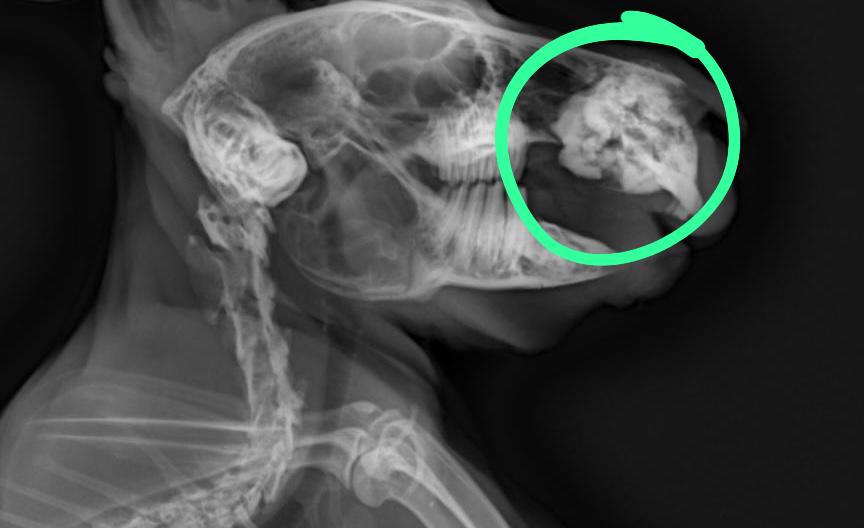

門牙感染、充滿膿液

牙根過長(食物太過多樣化、兔兔挑食誘發只食甜食,拒食硬草)

2. 影像檢查:X 光可評估腸道氣體、糞塊位置和牙齒結構;或需鎮靜。

• 牙科問題:在麻醉下修整牙齒,移除尖刺,或處理牙根膿腫。術後需服用止痛及抗生素。